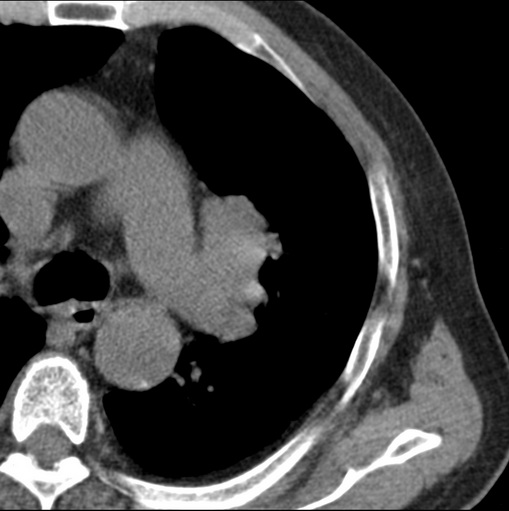

标题: CT25434:胸部CT增强扫描

男性患者 81岁 咳嗽 咳痰 咯血

肿块贴近左肺门,包绕左上肺动脉,形态不规则。肿块增强扫描中度强化。纵膈内主动脉弓左旁间隙、气管隆突前、下间隙见多枚淋巴结影。综上考虑左侧中央型肺癌可能性大。图片没有完整上传,尤其是左肺上叶支气管分支层面没有上传,因此不好判断是叶支气管中断还是段支气管中断。另外,下图红色部分所示是“黏液支气管征”吗?